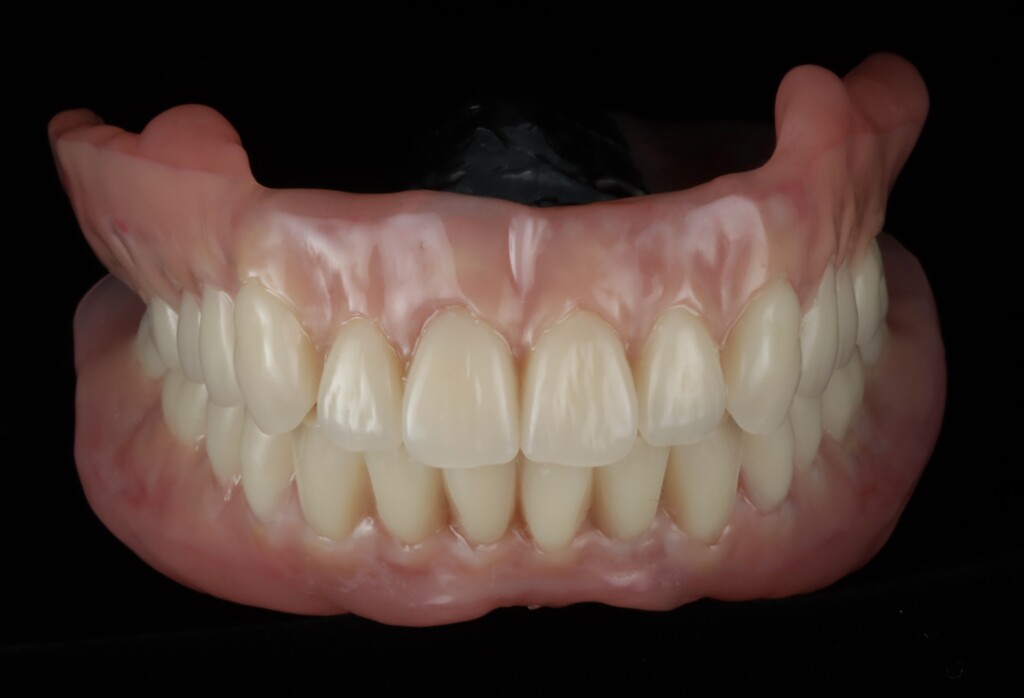

歯肉の質感まで再現された最終精密義歯

天然歯と見分けがつかない最終精密義歯

インプラントなしでも、ここまで動かない総義歯

- 真っ直ぐ噛んでも、横に歯を擦るように動かしても安定していることが左の動画で確認することができます

最終的には、入れ歯の安定性が向上し、食事の際のズレや不安も軽減され、日常生活における「噛める」という機能を取り戻すことができました。

「不安な時期もあったが、今は治療して本当に良かった。今までで一番快適な入れ歯です」